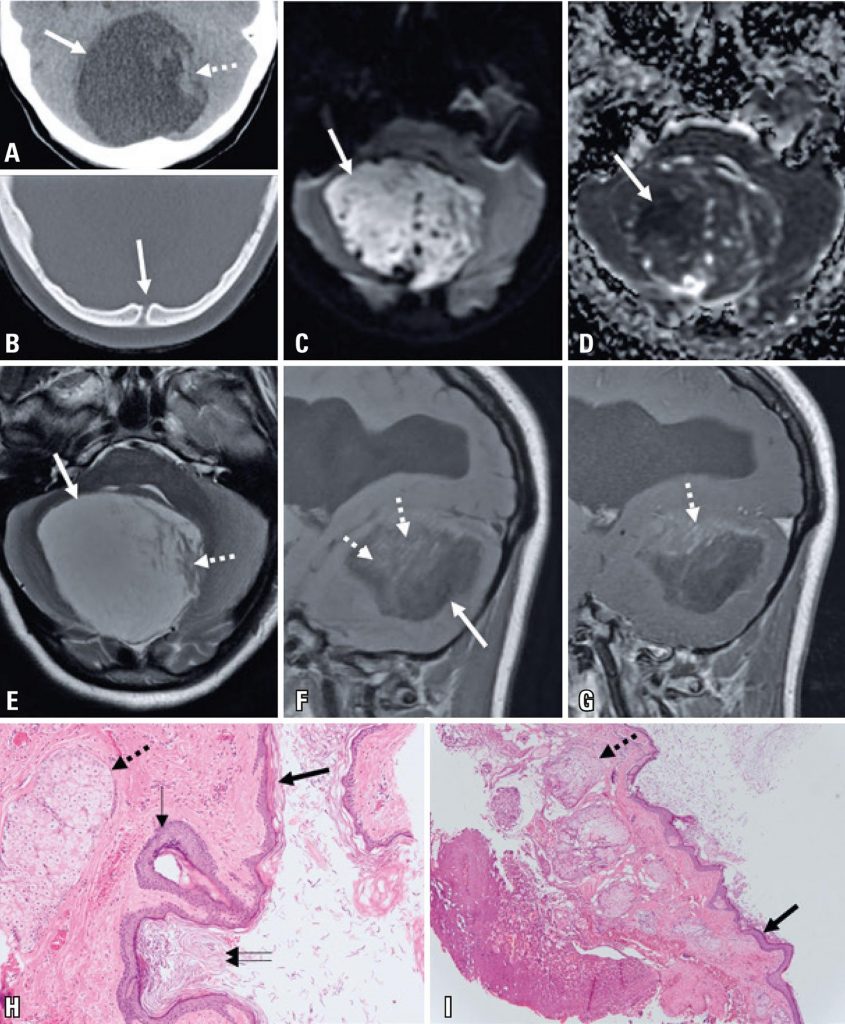

A 15-year old women presented with a 6-month history of progressive right-hand tremor with functional impairment, aggravated by a 1-month history of episodic confusion. The patient underwent a computed tomography scan, which revealed a posterior fossa expansive lesion with cerebrospinal fluid-like density and a midline bone discontinuity ( ; soft tissue window not shown). A magnetic resonance imaging (MRI) scan ( ) was performed after hospital admission, revealing a posterior fossa expansile lesion with predominant T2 hyperintensity, T1 hypointensity, linear and irregular areas of faint enhancement after gadolinium injection, and a large area with reduced water diffusion. Supratentorial images revealed signs of chronic hydrocephalus. The patient underwent surgery revealing a whitish extra-axial capsulated lesion containing dermal appendages, and histology confirmed the diagnosis of a dermoid cyst ( ).